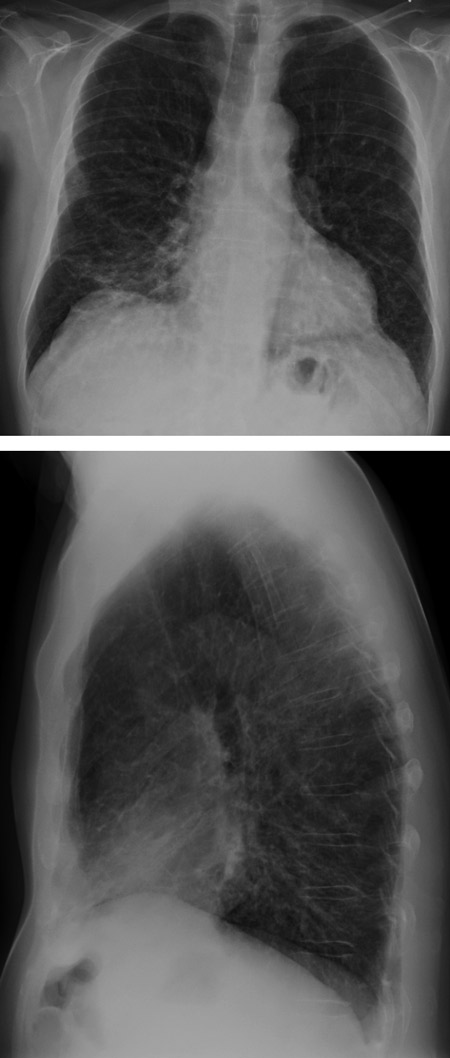

Pasienten hadde vel 20 år tidligere fått diagnosen sarkoidose basert på transbronkiale biopsier som viste granulomatøs betennelse. Ti år senere fikk han påvist immunsvikt av type vanlig variabel immunsvikt (common variable immune deficiency, CVID) og startet substitusjonsbehandling med immunglobulin. Utfall i biokjemiske leverprøver to år senere førte til leverbiopsi som viste granulomer forenlig med sarkoidose. De siste to år hadde pasienten tiltakende dyspné og respirasjonssvikt, og hadde startet med langtidsbehandling med oksygen. På henvisningstidspunktet viste arteriell blodgassanalyse (pO₂(a)) 7,1 kPa (10,0 – 14,0 kPa) med oksygen 3 l/min på nesekateter. Han trengte oksygen 8 l/min for å komme opp i pO₂ 8,0 kPa. Røntgen thorax var uendret over flere år og viste sparsomme fibrøse drag (fig 1). Spirometri var også uendret, med verdier midt i det forventede området. Gassdiffusjonskapasitet var imidlertid redusert til 48 % av forventet. Tre ukers behandling med prednisolon 20 mg daglig var forsøkt uten effekt på symptomer, lungefunksjon eller blodgasser. Han ble derfor henvist for vurdering av lungetransplantasjon, eventuelt optimalisering av behandling for sarkoidose.

Tilsendte røntgenundersøkelser fra henvisende sykehus ble revurdert. Som bifunn på CT av thorax/ øvre abdomen tatt ti måneder før innleggelse på Rikshospitalet ble det bemerket at det forelå åpentstående umbilikalvene samt slyngede vener i øvre abdomen som ga mistanke om portal hypertensjon (fig 2).